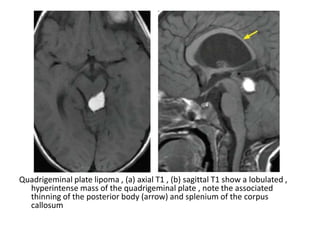

4-Quadrigeminal Plate Lipoma :

-At CT, lipomas have low attenuation, consistent

with fat

-At MR imaging, they have the same signal

characteristics as fat (hyperintense on T1 with

saturation on fat-saturated images)

-No enhancement is seen on postcontrast

images

Quadrigeminal plate lipoma , (a) axial T1 , (b) sagittal T1 show a lobulated ,

hyperintense mass of the quadrigeminal plate , note the associated

thinning of the posterior body (arrow) and splenium of the corpus

callosum

4-Quadrigeminal Plate Lipoma: -At CT, lipomas have low attenuation, consistent with fat -At MR imaging, they have the same signal characteristics as fat (hyperintense on T1 with saturation on fat-saturated images) -No enhancement is seen on postcontrast images

• 80.

Quadrigeminal plate lipoma, (a) axial T1 , (b) sagittal T1 show a lobulated , hyperintense mass of the quadrigeminal plate , note the associated thinning of the posterior body (arrow) and splenium of the corpus callosum